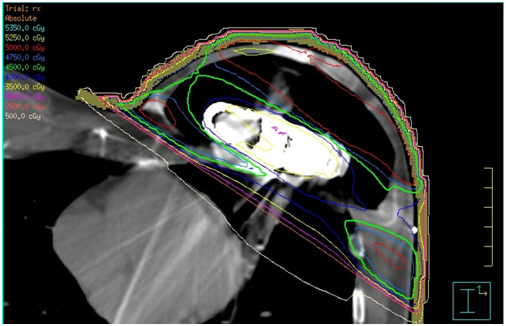

Figure 1 shows an example of an air expander in situ on a CT transverse slice. Between March 2016 and August 2018, data was collected prospectively from eight female patients fitted with the AeroForm™ implant who were referred to our institution for post-operative radiotherapy. The objective was to develop a treatment planning protocol using the Pinnacle3 Treatment Planning System (TPS) v9.10 (Philips, USA). All patients underwent a computed tomography (CT) scan as per our standard breast treatment simulation protocol on the Optima CT 580 RT (GE Healthcare) scanner. All treatment plans were generated for the Elekta Synergy linear accelerator with AgilityTM head (Elekta, Sweden), and collapsed cone algorithm beam modelling was carried out in the TPS. The slice thickness of all CT scans was 2.5 millimetres (mm), and these were calculated on a 3mm dose grid size in the TPS. The radiation oncologist defined the treatment area by marking the superior level, inferior level, medial border and posterior border on the patient. These borders defined the beam shape of the multi-leaf collimator (MLC) using the beams eye view in the TPS.

Density overrides were established by the planning team, to achieve the most accurate plan dosimetry as possible (Table 1). The values in Table 1 were dependent on CT density and the planning beam model. A three-dimensional conformal radiotherapy (3D CRT) wedged pair tangential planning technique was subsequently used to minimize the uncertainties (Figure 3).

Figure 1 AeroForm™ implant on a transverse slice CT scan. Main components visible are the centrally placed CO2 canister encompassed by a permeable silicone casing.

Figure 3 Transverse slice of 3D CRT wedged tangential beams applied for planning in Pinnacle3.